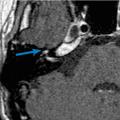

Nécessaire et utile, une audiométrie avec tympanométrie et étude des réflexes stapédiens est précieuse. Depuis les dernières recommandations de la Société française d’ORL (SFORL),6 une IRM injectée (sans urgence) est aussi préconisée. Les formes virales se caractérisent par une prise de contraste importante et focalisée du ganglion géniculé et des portions avoisinantes du nerf facial (fig. 3). Le scanner n’est indiqué qu’en cas d’otoscopie anormale, à la recherche d’une pathologie de l’oreille moyenne ou du rocher.